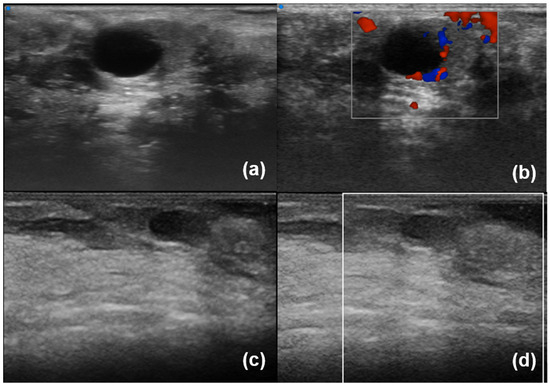

| Ferro et al. (2020) [35] | B-mode | SjD diagnostic value (SjD patients have higher inhomogeneity) Associations of inhomogeneity with Ro/SSA+ positivity Correlationsof inhomogenity with histological inflammation |

| Izzetti et al. (2021) [20] | B-mode | Support to the biopsy procedure |

- Izzetti, R.; Ferro, F.; Vitali, S.; Nisi, M.; Fonzetti, S.; Oranges, T.; Donati, V.; Caramella, D.; Baldini, C.; Gabriele, M. Ultra-high frequency ultrasonography (UHFUS)-guided minor salivary gland biopsy: A promising procedure to optimize labial salivary gland biopsy in Sjögren’s syndrome. J. Oral Pathol. Med. 2021, 50, 485–491. [Google Scholar] [CrossRef]

- Ferro, F.; Izzetti, R.; Vitali, S.; Aringhieri, G.; Fonzetti, S.; Donati, V.; Dini, V.; Mosca, M.; Gabriele, M.; Caramella, D.; et al. Ultra-high frequency ultrasonography of labial glands is a highly sensitive tool for the diagnosis of Sjögren’s syndrome: A preliminary study. Clin. Exp. Rheumatol. 2020, 38 (Suppl. S126), 210–215. [Google Scholar]

- Fulvio, G.; Donati, V.; Izzetti, R.; Fonzetti, S.; La Rocca, G.; Ferro, F.; Baldini, C. Correspondence between minor salivary glands ultra-high frequency ultrasonography and histology: A case report of severe/atypical lymphoid infiltrate in Sjögren’s syndrome. Ann. Rheum. Dis. 2022, 40, 2474–2475. [Google Scholar] [CrossRef]